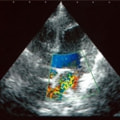

C:超音波 僧帽弁逆流のカラードップラー画像

左側胸壁心尖部領域を最強点とするLevine 5/6の収縮期性心雑音が聴取された。安静時にも咳が認められる。胸部レントゲン検査において重度の心拡大が及び肺水腫が認められた。超音波検査では、重度の僧帽弁閉鎖不全、三尖弁閉鎖不全が認められた。三尖弁逆流速度から肺高血圧症が示唆された。ACE阻害薬、ピモベンダン、硝酸イソソルビド徐放剤、ベラプロストナトリウム、利尿剤としてフロセミド及びスピロノラクトンを用いて治療を行っている。